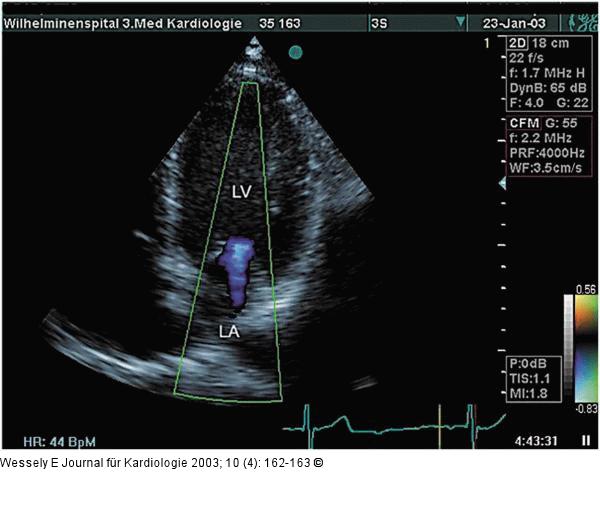

Abbildung 1: Mitralinsuffizienz Apikaler Vierkammerblick, inkomplette Schlußstellung der Mitralklappe, diastolisches Regurgitationssignal bei AV-Block III (LA = linker Vorhof, LV = linker Ventrikel)) |

Apikaler Vierkammerblick, inkomplette Schlußstellung der Mitralklappe, diastolisches Regurgitationssignal bei AV-Block III (LA = linker Vorhof, LV = linker Ventrikel)) |